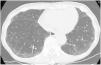

“Indeterminate for UIP”: Features of fibrosis are demonstrated but does not meet UIP or probable UIP criteria and does not explicitly suggest an alternative diagnosis (Fig. 3). This includes patients with very limited subpleural ground-glass opacification or reticulation without obvious CT features of fibrosis, for whom there is a suspicion that early UIP or probable UIP is present. In such cases, it should be confirmed with prone inspiratory views that the subpleural opacities do not represent dependent atelectasis.

Figure 3.This CT images shows only minor subpleural interstitial changes, to be classified as “indeterminate for UIP”. To exclude a gravity dependency prone images were acquired showing the same changes. These changes show no honeycombing. Mild peripheral bronchiectasis are being noted indicative for a fibrotic component.